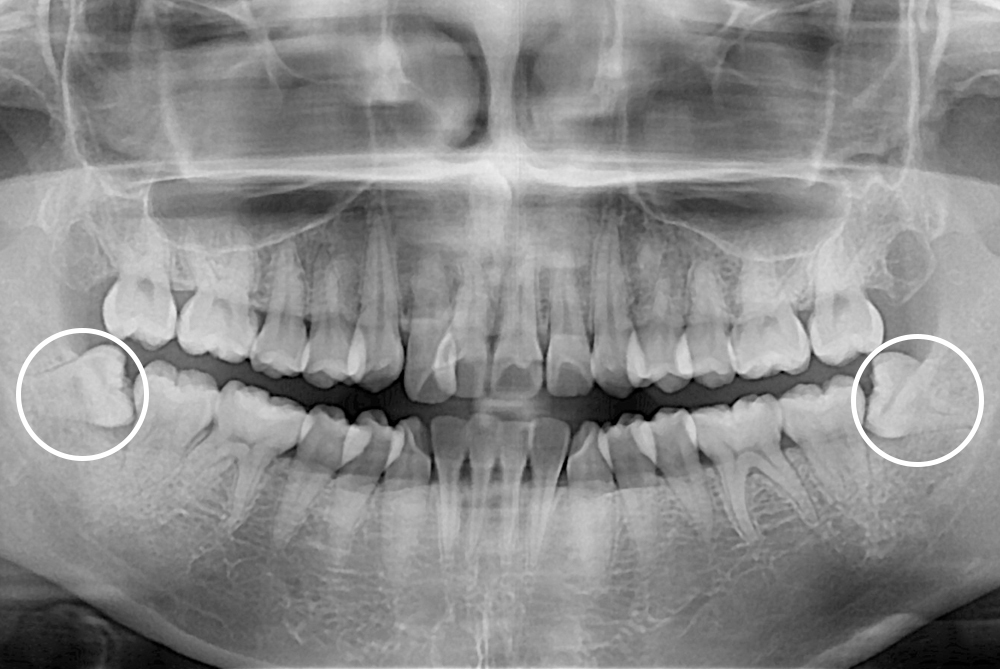

[사랑니] 매복 사랑니 발치

치료전 : 2018-05-15

세종치과는 구강악안면외과학 박사이신 원장님이 발치하는 치과입니다.